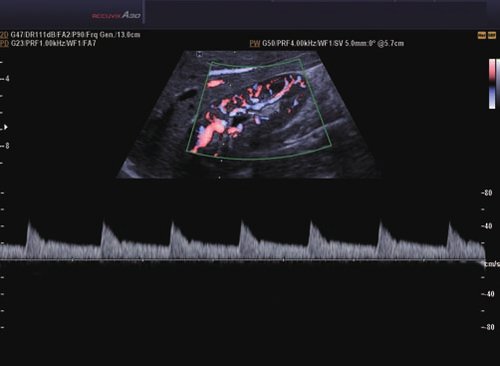

• Farb-Doppler

• Pulsed Wave (PW)-Spektral-Doppler

• Continuous Wave (CW)-Doppler

• Power-Doppler (PD)

• Directional Power Doppler (DPD)

• Color Opt Flow™ bietet kraftvollere Farben und verbessert die Bildqualität.